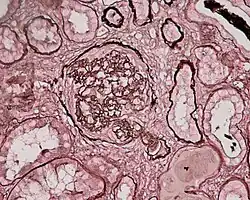

Crescentic glomerulonephritis induced by infective endocarditis on PAS staining and immunofluorescence. PAS staining (left) demonstrated circumferential and cellular crescent formation with interstitial nephritis. Immunofluorescence (right) demonstrated C3 positive staining in mesangial area.

Photomicrograph of renal biopsy showing crescent formation and tuft narrowing. Periodic acid silver methenamine stain.

Rapidly progressive glomerulonephritis, also known as crescentic GN, is characterised by a rapid, progressive deterioration in kidney function. People with rapidly progressive glomerulonephritis may present with a nephritic syndrome. In management, steroid therapy is sometimes used, although the prognosis remains poor.[9] Three main subtypes are recognised:[4]: 557–558

Histopathologically, the majority of glomeruli present "crescents". Formation of crescents is initiated by passage of fibrin into the Bowman space as a result of increased permeability of glomerular basement membrane. Fibrin stimulates the proliferation of endothelial cells of Bowman capsule, and an influx of monocytes. Rapid growing and fibrosis of crescents compresses the capillary loops and decreases the Bowman space, which leads to kidney failure within weeks or months.